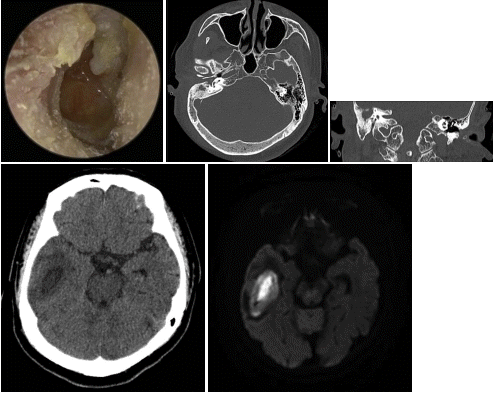

60세 여자 환자가 내원 10일 전부터 시작된 이통과 두통을 주소로 내원하였다. 인근 병원에서 약을 처방받았으나 호전이 없었고 두통은 더 심해지는 양상이었다. 환자의 고막 소견 및 시행한 temporal bone CT와 brain CT, MRI 소견은 다음과 같았다. 다음 중 이 질환에 대한 설명으로 맞지 않는 것은?

해설 만성 중이염의 합병증으로 발생한 뇌농양의 모습이다. 중이염은 선천성 심장 질환, 두부 손상이나 신경외과적 수술 다음으로 세 번째 흔한 뇌농양의 원인이다. 유양돌기에는 인접하지 않는 경우가 대부분이며, 측두엽 농양이 더 흔하지만 소뇌농양의 경우 사망률이 더 높은 경우가 많다. 주로 고실천장의 골염에 의해서 생긴 경막외농양의 악화로 발생하거나 유양돌기에 인접한 정맥통로를 통해 뇌실질로 전파된다. 광범위항생제와 덱사메타손 정맥주사를 병용하며, 입원 24시간 이내 신경외과적 배농 또는 농양절제술을 시행하고 환자 상태가 호전되면 별개의 수술 접근법을 통해 유돌절제술을 하는 것이 원칙이다.